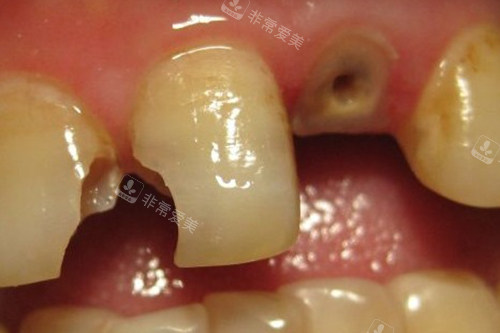

牙齿龋坏钻洞实拍

牙齿龋坏到牙根

牙齿龋坏根管治疗前

清理龋坏照片